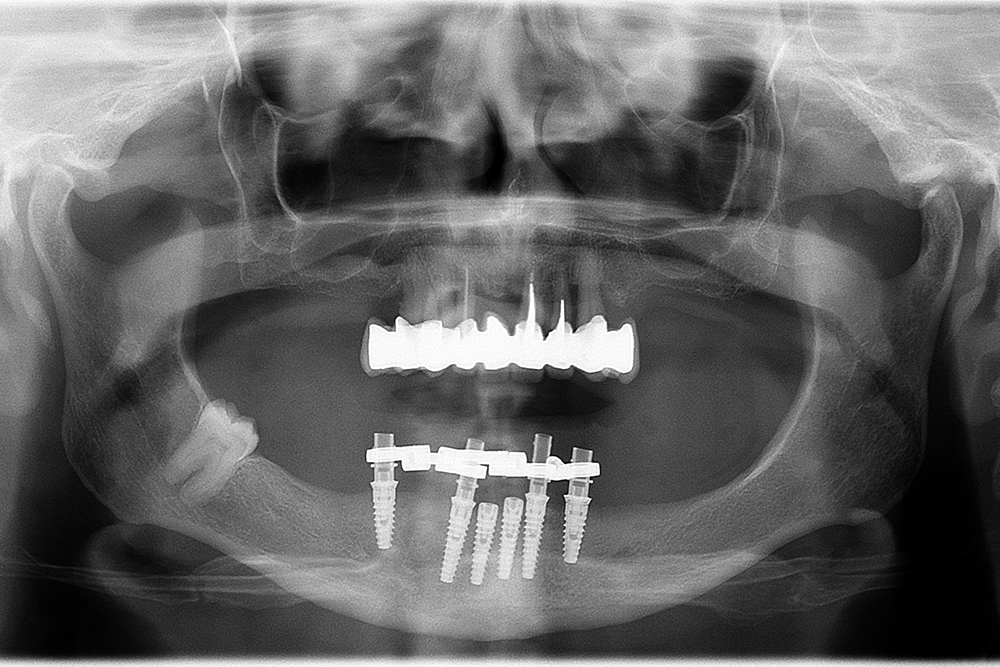

Ripristino dell'arcata inferiore con carico immediato Category: Lavori ImpiantiMaggio 9, 2018Condividi questo ProgettoShare with FacebookShare with TwitterShare with Google+Share with PinterestShare with LinkedInProject navigationPreviousPrevious project:Ripristino dell’arcata superiore su impiantiNextNext project:Ripristino di breccia anteriore inferiore